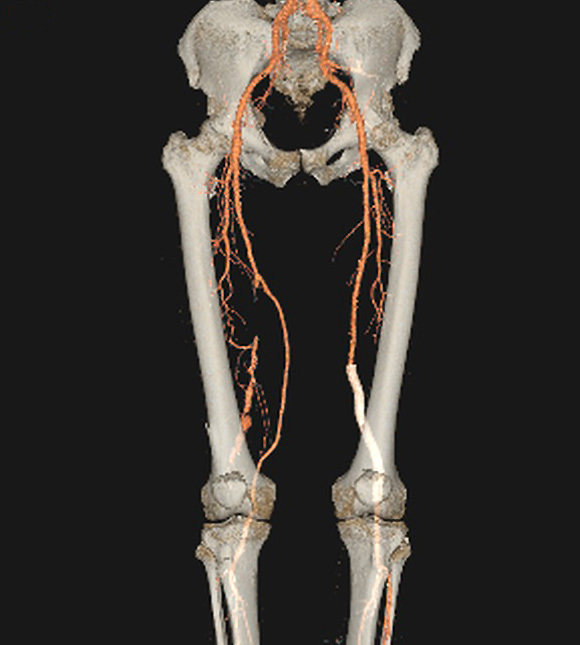

Aneurisma de poplítea bilateral tratado à direita com "bypass" de safena e à esquerda com endoprótese